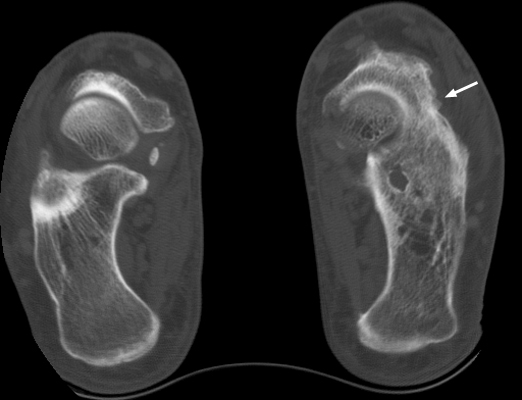

Plain film and CT images of calcaneonavicular coalition. Notice the elongated, tubular like extension of the anterior calcaneus seen on the lateral film; this imagery has been likened to the elongated nose of an anteater. There is abnormal bony fusion of the calcaneus and navicular bones, with the presence of a bony bar extending between these two bones.

- Click on the image for a larger versionALateral foot - Click on the image for a larger versionBCT - Click on the image for a larger versionC